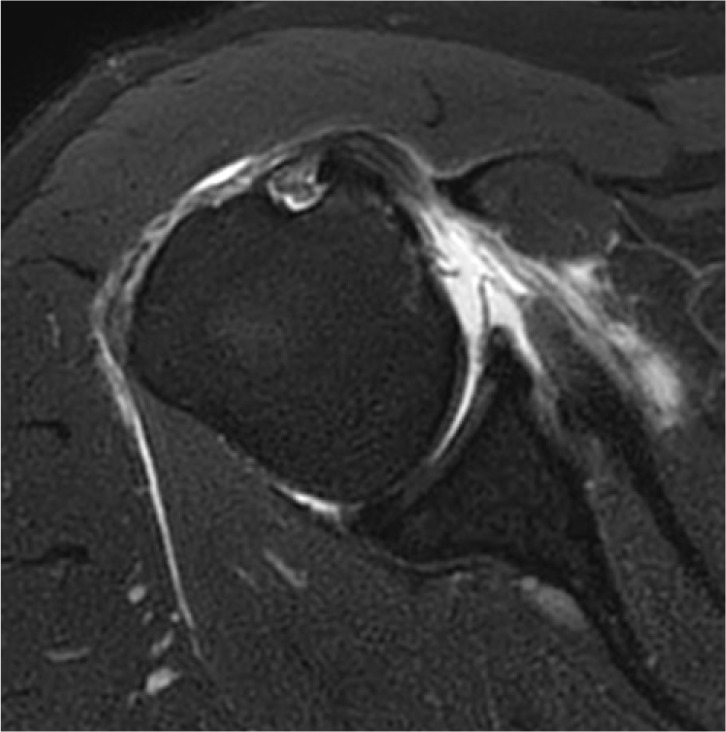

肩部疾病,包括粘连性囊炎、肩袖撕裂和肩关节骨关节炎,可严重损害老年成人患者的日常活动。本综述旨在探讨老年患者这些肩关节疾病的影像学表现,为准确诊断和有效治疗提供见解。粘连性囊炎,俗称冻肩,导致疼痛和活动受限,从而引起肩关节功能障碍。最近诊断技术的进步极大地提高了通过放射学评估诊断这种疾病的敏感性和准确性,包括MRI,磁共振关节成像(MRA)和高分辨率超声。肩袖疾病是老年人的另一个常见问题,50%-80%的病例发生全层撕裂。MRI和MRA在识别肩袖撕裂方面都是高度敏感和特异性的。此外,超声在检测冈上肌腱撕裂方面具有很高的敏感性和特异性。虽然肩关节骨关节炎不太常见,但其晚期可严重影响上肢的功能。x线平片通常是评估这类骨关节炎的首选成像技术。随着病情的恶化,CT被用于测量关节盂骨丢失、关节盂形态和关节盂倾斜度,这对于精确的手术计划至关重要。每种成像方式都有其独特的优势:x线平片用于初始结构评估,超声检查用于软组织的实时评估,MRI/MRA用于详细可视化囊和肌腱病变,CT用于精确的骨骼分析。

Shoulder diseases, including adhesive capsulitis, rotator cuff tear, and osteoarthritis of the glenohumeral joint, can significantly impair daily activities in older adult patients. This review aims to examine the radiologic findings associated with these shoulder conditions in older patients, providing insights for accurate diagnosis and effective treatment. Adhesive capsulitis, commonly known as frozen shoulder, leads to pain and restricted movement, thereby causing shoulder dysfunction. Recent advances in diagnostic technology have greatly enhanced the sensitivity and accuracy of diagnosing this condition through radiologic evaluations, including MRI, magnetic resonance arthrography (MRA), and high-resolution ultrasound. Rotator cuff disease is another frequent issue in older adults, with full-thickness tears occurring in 50%-80% of cases. Both MRI and MRA are highly sensitive and specific in identifying rotator cuff tears. Additionally, ultrasonography is recognized for its high sensitivity and specificity in detecting tears of the supraspinatus tendon. Although osteoarthritis of the glenohumeral joint is less commonly prevalent, its advanced stages can severely affect the function of the upper extremity. Plain radiography is typically the first imaging technique used to assess this type of osteoarthritis. As the condition worsens, CT is utilized to measure glenoid bone loss, glenoid version, and inclination, which are crucial for accurate surgical planning. Each imaging modality provides distinct benefits: plain radiographs for initial structural assessment, ultrasonography for real-time evaluation of soft tissues, MRI/MRA for detailed visualization of capsular and tendinous lesions, and CT for precise bony analysis.